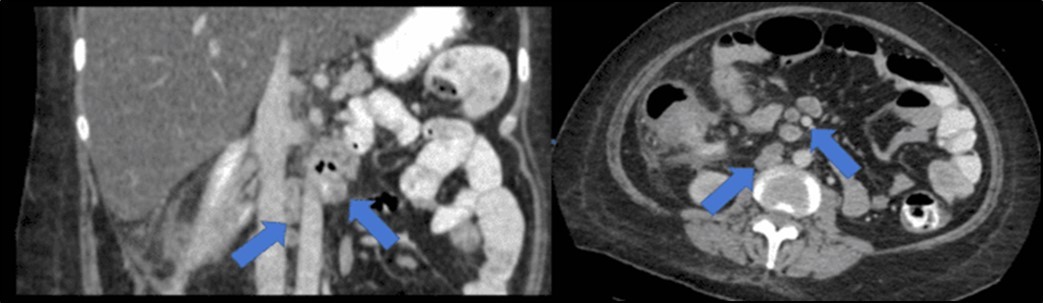

There was no evidence of malignancy or IBD seen during both endoscopic procedures. Computed tomography (CT) scan of the whole abdomen was done which showed inflammatory changes involving the cecum and adjacent duodenum and ileum with coloenteric fistulae. There was noted progression of abdominal lymphadenopathies as well as ascites. Main consideration was an infectious disease process (i.e. TB) (Figure 2, Figure 3, Figure 4 to Figure 5).

Figure 4.Coronal and axial view of the abdomen, the blue arrows pointing towards the suggestive communication to the duodenum

Coronal and axial view of the abdomen, the blue arrows pointing towards the suggestive             communication to the duodenum

Figure 5.Enlarged and necrotic abdominal nodes in the mesenteric, pericecal, pericolic, para-aortic, paracaval and inter-aortocaval regions. Prominent and enlarged nodes also located in the common hepatic and periportal regions

Enlarged and necrotic abdominal nodes in the mesenteric, pericecal, pericolic, para-aortic, paracaval and inter-aortocaval regions. Prominent and enlarged nodes also located in the common hepatic and periportal regions